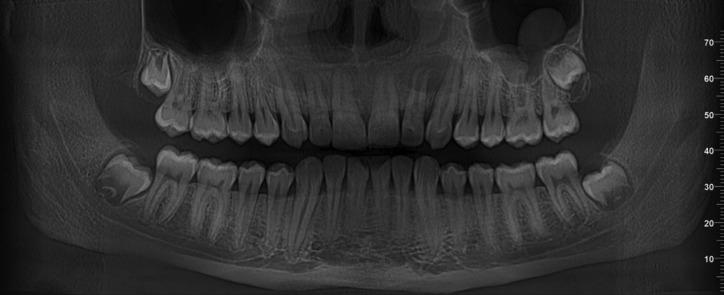

The clinical results and Panoramic X-ray evaluation at three months postoperatively were very promising.

术后三个月的临床结果和全景X线评估非常乐观。